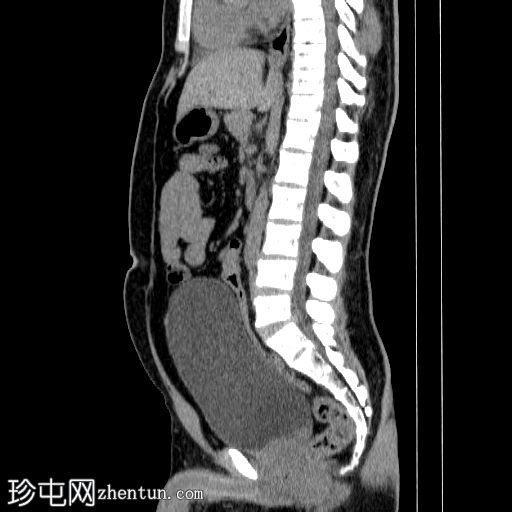

矢状位

平扫

双侧肾结石,无梗阻,较大结石位于左侧肾下盏,最大直径约4 mm,平均CT值约730 HU,伴左侧输尿管轻度扩张。

膀胱明显充盈,高度达脐部,若患者无法排尿,可能需要导尿。

患者主诉左侧肾绞痛,既往有肾结石病史。